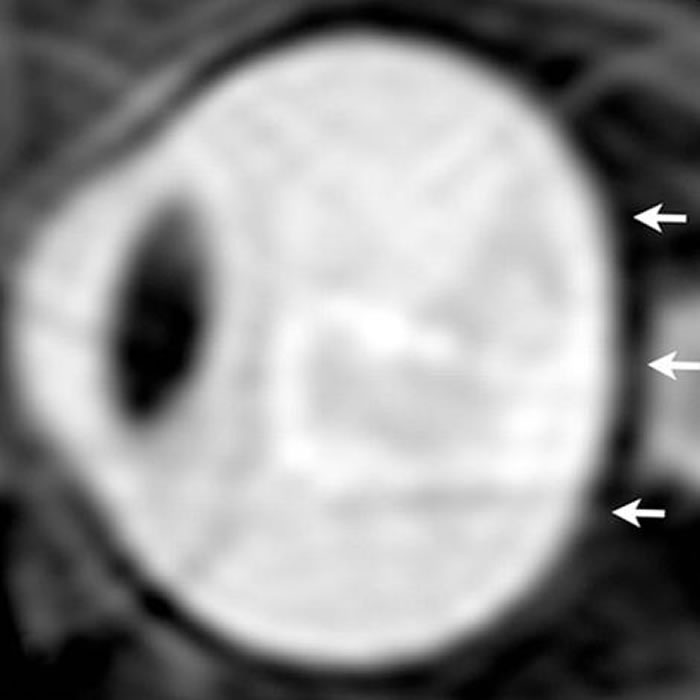

太空人眼部的核磁共振图。在长期的太空生活之后,太空人的眼球出现被挤压扁平的状况。 PHOTOGRAPH BY RSNA

他们发现在太空中待上数月的七名太空人的眼窝内普遍发现较多量的脑脊髓液。这让太空人眼球后方承受了更多压力,造成眼球后方挤压,进而导致视神经突出。